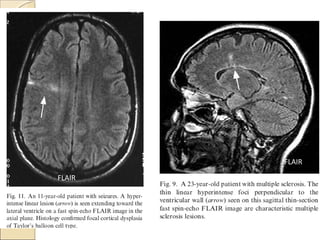

Fluid-attenuated inversion recoveryFluid-attenuated inversion recovery

(FLAIR)(FLAIR)

First described in 1992 and has become

one of the corner stones of brain MR

imaging protocols

An IR sequence with a long TR and TE

and an inversion time (TI) that is tailored

to null the signal from CSF

Particularly helpful in evaluating

periventricular white matter lesion.

Effective in high lightening lesion…

demyelination, stroke, Ischemic gliosis

and tumor

T2 W

FLAIR